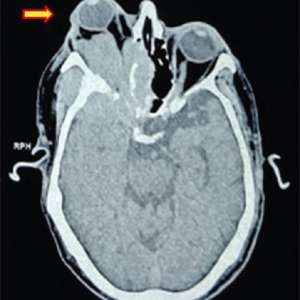

Мужчина, 72 года

Обратился к офтальмологу с жалобами на двоение в глазах и боль в правом глазу, которые беспокоят его в течение шести месяцев. При осмотре был выявлен экзофтальм с ограничением подвижности правого глаза.

КТ: правосторонний экзофтальм, а также обширное деструктивное мягкотканное образование с вовлечением клиновидной кости (большого и малого крыльев), правой глазницы, лобно-височной части черепа с интраконическим, экстраконическим, интрасинуальным и инфратемпоральным пролабированием мягких тканей (рис. 1)